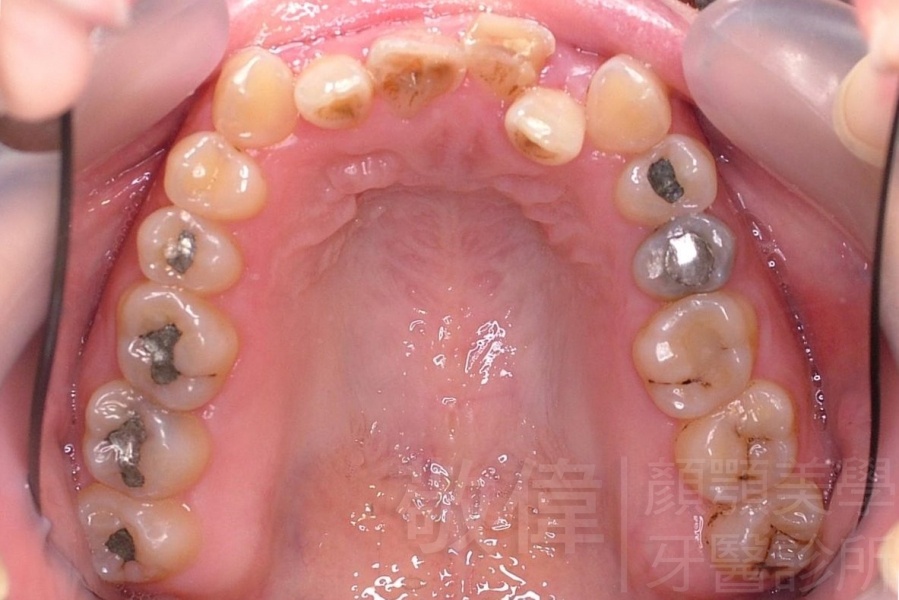

齒顏矯正/戽斗、亂牙、爛牙,變身 免植牙的健牙美女

<個案說明>

變臉矯正,原來戽斗妹跟大歪臉變成自信正妹

經由本院3D數影X光影像儀分析、與3D齒顎顏矯正技術,再配合口腔顎面正顎專科醫師施以正顎手術治療,雙方共同合作,使患者臉部外觀有很好的改善,大歪變小歪,產生了天南地北的大改變,她的人生也整個變得不一樣。